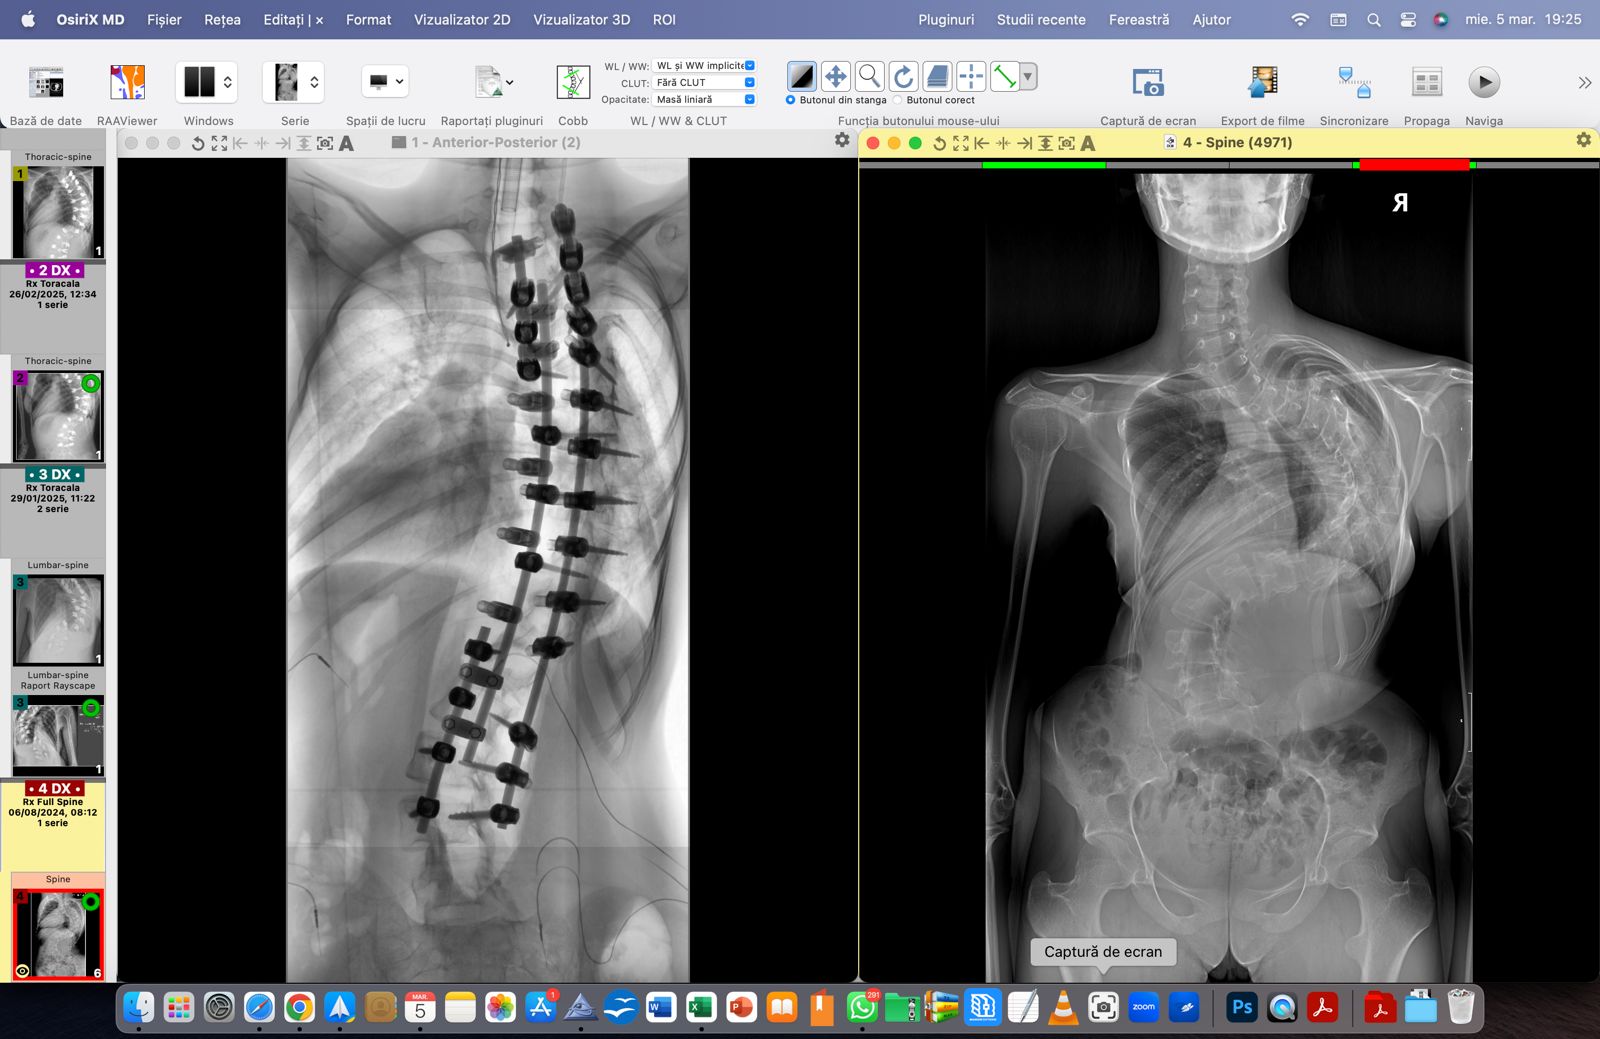

Denisa – o luptătoare de doar 15 ani – se întoarce acasă! Cu inima plină de recunoștință și cu speranță în suflet. După două intervenții dificile, un unghi Cobb de 143° a devenit 57°! O diferență uriașă care înseamnă nu doar o coloană mai dreaptă, ci o viață nouă, o șansă reală la normalitate.

Bani care s-au adunat în cele din urmă datorită oamenilor cu suflet mare care au adunat pentru Denisa, fetița care a fost diagnosticată cu o formă gravă de scolioză.